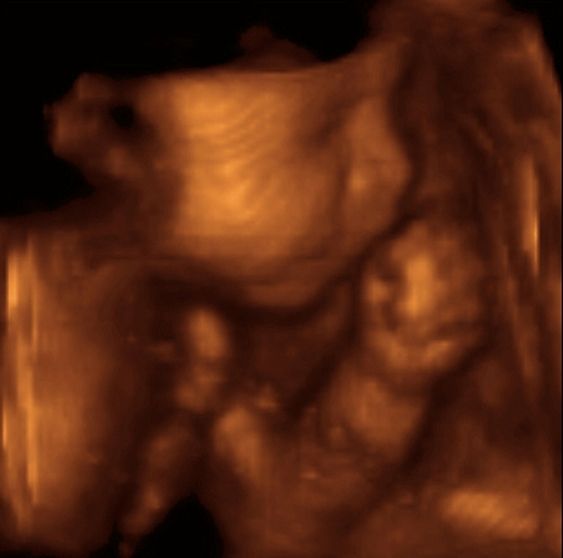

La calidad de las condiciones en las que un bebe pasa las nueve lunas en el vientre materno determinará la vulnerabilidad o la fortaleza que desarrollará su organismo en los años que le toque vivir.

«La mayoría de los órganos se completan al nacer -continuó-, de manera tal que la etapa más importante de nuestra vida es en el útero, donde se va «construyendo» el organismo. Por lo tanto, si queremos prevenir la diabetes, la hipertensión, los accidentes cerebrovasculares y las enfermedades cardíacas, tenemos sí o sí que mejorar la nutrición del bebe.»